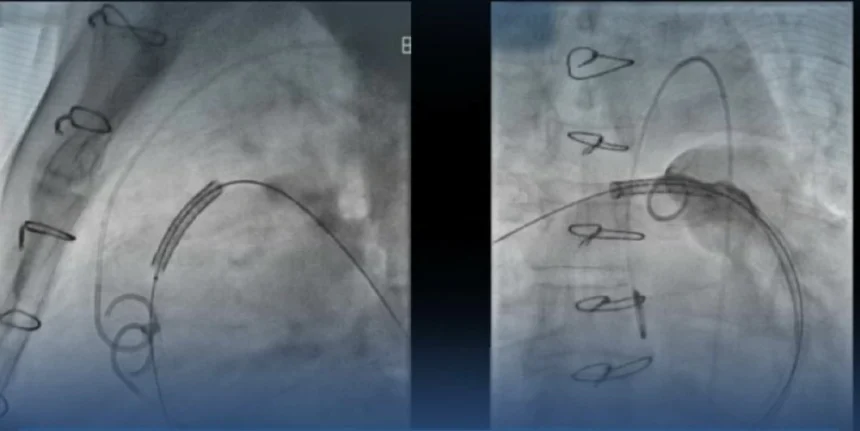

سجّل التجمع الصحي في منطقة حائل إنجازاً طبياً جديداً بعد نجاح تركيب أول صمام رئوي عبر القسطرة في المناطق الشمالية في مستشفى الملك سلمان التخصصي، ضمن عملية قادها استشاري القلب والقسطرة ومشرف مسار القلب في تجمع حائل الصحي الدكتور نايف الغصاب، بمشاركة طاقم سعودي متخصص في جراحات القلب التداخلية.

وقال الدكتور الغصاب: بحمد الله، نجحنا في تركيب أول صمام رئوي في المناطق الشمالية لعلاج تضيق وارتجاع الصمام الرئوي. تمثل هذه الخطوة نقلة نوعية في نجاح التجمع الصحي في رعاية مرضى العيوب الهيكلية وصمامات القلب. هذا التطور يعكس حرص حكومتنا الرشيدة لدعم توفير خدمات علاجية مميزة للمواطن.

العملية جاءت بجهود فريق محلي مؤهل في التخدير والأشعة والتمريض التداخلي، ما يؤكد قدرة الكفاءات السعودية على قيادة الإجراءات عالية الدقة.

أجريت العملية باستخدام تصوير متقدم ودعامات عالية الضغط تضمن الدقة والنتائج المثالية، ليعزز هذا النجاح مكانة مركز القلب كوجهة علاجية رائدة في أمراض العيوب الهيكلية وصمامات القلب.